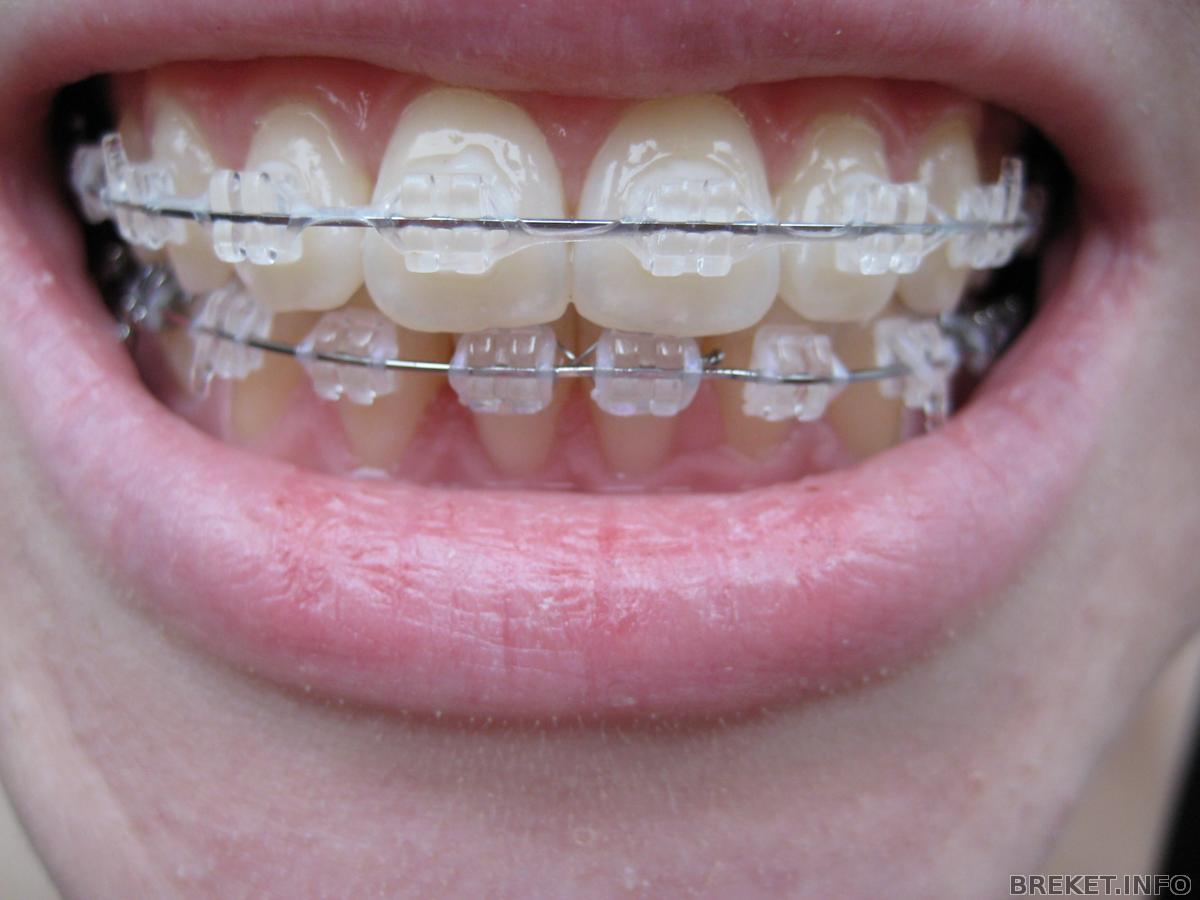

Была на приеме. Поменяли лигатурки, поставила прозрачные вместо розовых) Зубки выглядят по-другому сразу.

Между 1-ми на НЧ была щель, завязали это дело проволочкой, щель моментально испарилась, но появилась щель между 1-ей и 2-ой((( Буду снова "дырявая ходить" ![]()

Тягу с одной стороны отменили, ибо перетянули уже, будет разбегаться теперь само, с другой стороны и для центра продолжаем носить.

С функциональной частью мы закончили и в принципе можно уже просто стянуть все зубы, чтобы убрать щели и снимать (это радует конечно). НО теперь будем работать над "красотой", т.е. над тем, что НЕ нравится лично МНЕ. Радостно, что орта не настаивает на снятии и дает время поработать над эстетикой, чтобы мы не жалели о снятии.